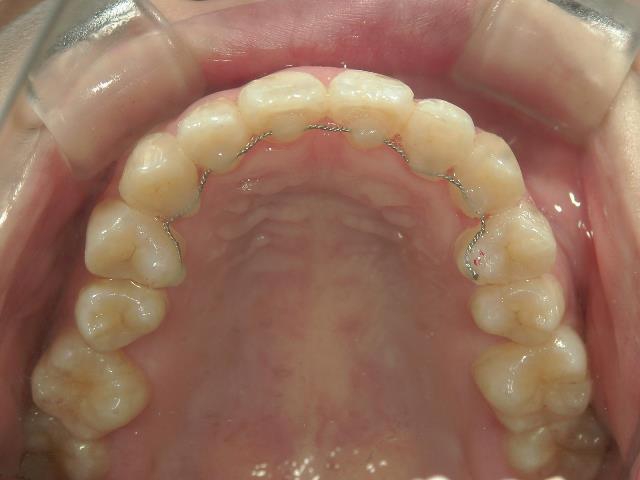

矯正歯科 治療後

矯正_灰色.pngno.8_8495_治療後_上.jpg矯正_灰色.png

no.8_8495_治療後_左.jpgno.8_8495_治療後_正面.jpgno.8_8495_治療後_右.jpg

矯正_灰色.pngno.8_8495_治療後_下.jpg矯正_灰色.png